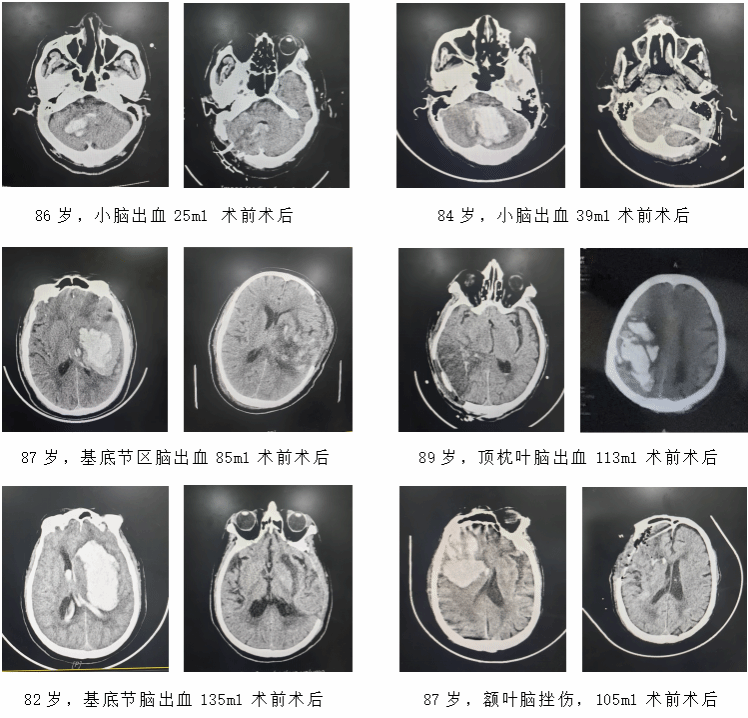

在医学领域,高龄、多种基础病、急危重脑出血——这三个因素叠加,常被视为救治的“禁区”,意味着极高的死亡与重残风险。然而,近期,我院神经外科联合多学科团队,以精湛的技术、缜密的协作与不放弃的坚守,成功为六位年龄均超过80岁的极危重脑出血患者实施手术并护航康复,创造了生命奇迹。这组病例,不仅是对专科技术的考验,更是对我院急危重症救治体系、围手术期精细管理及复杂并发症处理能力的全面检阅。

这六位高龄患者,年龄跨度82岁到89岁,平均年龄86岁,入院时均因突发意识障碍、偏瘫或生命体征不稳送至我院急诊。影像检查揭示了夺命的病灶:大量小脑出血、基底节区巨大血肿、顶枕叶出血破入脑室……每一种都是神经外科的急重症。但与普通患者不同,当“脑内风暴”遇上“满身旧账”,风险暴增,他们每个人都背负着一身“旧账”:严重的心功能不全、肺大泡与慢性阻塞性肺疾病(COPD)、慢性肾功能不全、长期高血压与糖尿病等。脆弱的脏器功能,使得麻醉风险呈几何级数攀升,手术耐受性极差,术后任何一个环节的并发症都可能是致命一击。